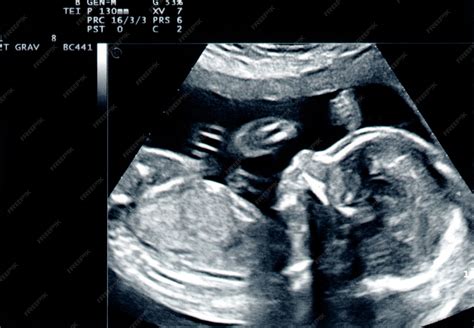

Das Erst-Trimester-Screening (ab 12. Woche) erlaubt eine Abschätzung, ob beim Embryo ein erhöhtes Risiko für eine Trisomie 21 vorliegt. Es ergibt sich ein individuelles Risiko für die jeweilige Schwangerschaft, das deutlich präziser als das alleinige altersbedingte Risiko ausfällt. Neben der Trisomie 21 (Down-Syndrom) wird auch ein Risikowert für die Trisomie 18 (Edwards-Syndrom) und die Trisomie 13 (Pätau-Syndrom) angegeben.

Beim Erst-Trimester-Screening wird mittels Ultraschall im Bereich des Nackens nach vermehrter Wassereinlagerung gesucht (Nacken-Transparenzmessung; NT-Messung). Zusätzliche Blutparameter der Mutter (biochemisches Screening: freies ß-hCG und PAPP-A) erhöhen die Genauigkeit. Hundertprozentige Sicherheit gibt das Erst-Trimester-Screening nicht, da ausschließlich etwa 90 bis 95 Prozent der Schwangerschaften mit einer Trisomie 21 im Erst-Trimester-Screening auffällig werden. Die Wahrscheinlichkeitsangabe des Erst-Trimester-Screenings dient jedoch vielen werdenden Eltern als Entscheidungshilfe für oder gegen eine invasive Diagnostik (Fruchtwasserpunktion oder Chorionzottenbiopsie).